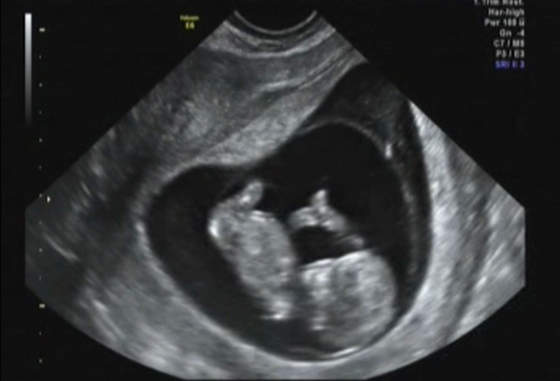

wzrost miał wtedy 6,9 cm ale to było tydzień temu wtedy to był 12t 3d, teraz jest 13t3d...